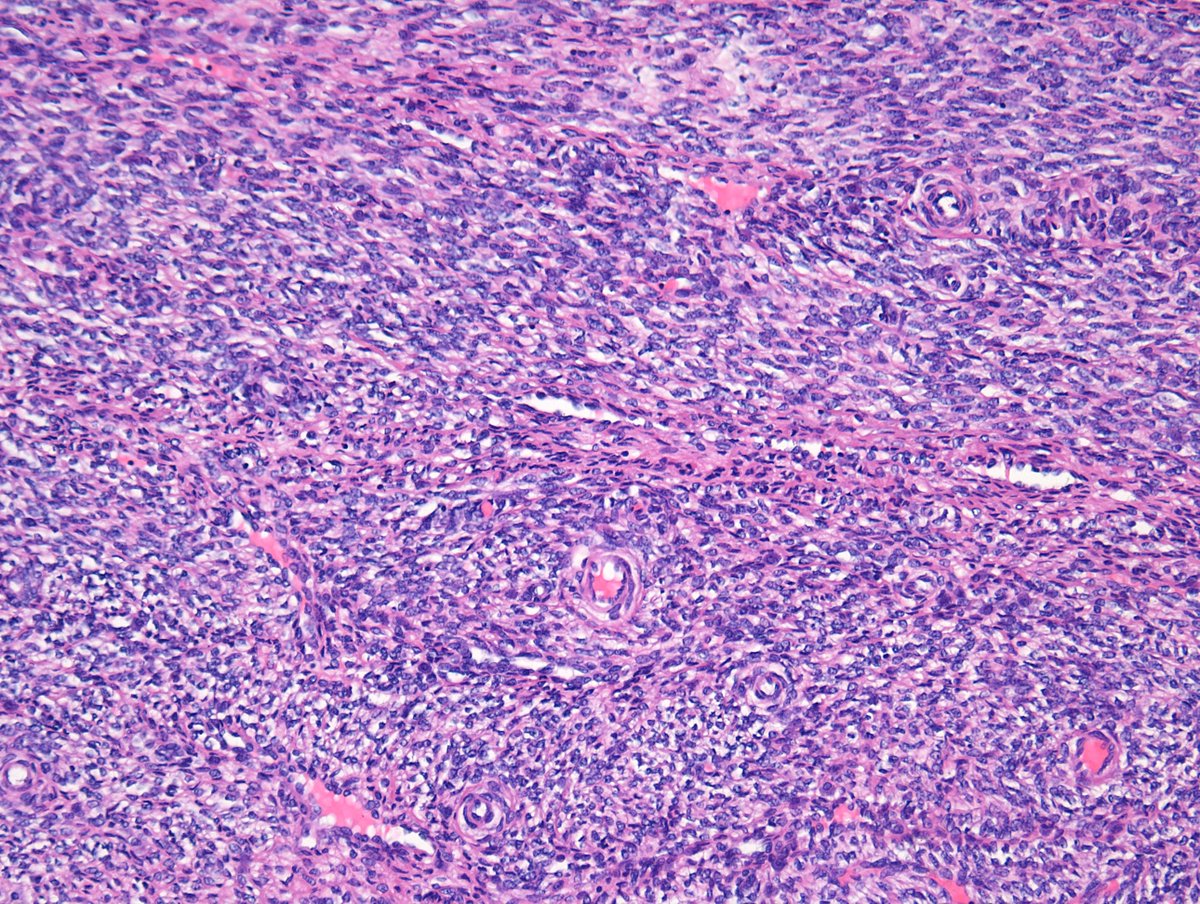

20+ male with a well circumscribed subcut abdominal mass, associated with osteoclast-type giant cells, foamy histiocytes, fibrous pseudocapsule, and bland ovoid cells. Focal keratin positivity. What is your diagnosis? ClevelandClinicLabs Cleveland Clinic Pathology Residency #BSTpath #pathology